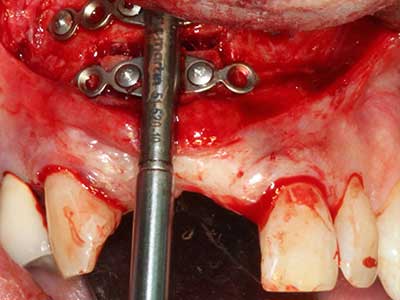

La piezochirurgia presenta altri vantaggi per quanto riguarda la raccolta di blocchi ossei. Oltre all'elevata precisione dell'osteotomia appena descritta, l'utilizzo di puntine per sega molto sottili permette di minimizzare in maniera significativa la perdita di materiale. È molto probabile che si verifichi una maggiore perdita di materiale durante la raccolta utilizzando puntine di strumenti più spessi, in particolare delle frese Lindemann (Lakshmiganthan, Gokulanathan et al. 2012). La separazione basale, necessaria in particolare per i trapianti di blocchi nella zona retromolare, viene semplificata grazie a seghe specificatamente progettate di forma rettangolare; di conseguenza la piezochirurgia è considerata una procedura precisa, semplice e sicura per la raccolta di blocchi di osso nella zona retromolare (Happe 2007) (figg. 1-12).

Il tessuto osseo non è semplicemente una struttura minerale, ma contiene anche una percentuale significativa di fibre di collagene. Ciò significa che non possiede solo una buona forza di compressione, ma anche un certo livello di flessibilità che è possibile sfruttare durante l'esecuzione degli accrescimenti di osso. Nella procedura di espansione classica con incisione ossea, la cresta alveolare atrofizzata viene incisa longitudinalmente ed espansa con cautela dopo aver raggiunto una profondità di osteotomia adeguata (figg. 13-16), idealmente senza una sostanziale rimozione del periostio (Brugnami, Caiazzo et al. 2014, Stricker, Fleiner et al. 2014). I sistemi a piastra e vite con distanza di espansione incrementale si sono dimostrati efficaci nella separazione delle due lamelle ossee restando al di sotto della soglia di frattura. In generale, sono richieste larghezze dell'osso residuo di almeno 3-4 mm (Chiapasco, Zaniboni et al. 2006) per garantire un'adeguata flessibilità e una copertura sufficiente dell'osso per gli impianti futuri. Se necessario, un'osteotomia di rilascio verticale su uno o più lati può migliorare la flessibilità. Una combinazione con ulteriori tecniche di accrescimento, in particolare dal lato buccale, è stata descritta come un'alternativa alla tecnica classica.

La procedura di incisione è particolarmente atraumatica e non comporta una perdita significativa di dimensione durante l'utilizzo delle seghe piezoelettriche, così come non si notano differenze rilevanti tra impianti in mandibole incise e impianti in una cresta alveolare senza deficit osseo (Chiapasco, Zaniboni et al. 2006, Danza, Guidi et al. 2009). Una sufficiente irrigazione continua è essenziale, tuttavia, in particolare con incisione profonda e localmente ristretta, per prevenire la sollecitazione termica nelle regioni apicali dell'osteotomia.